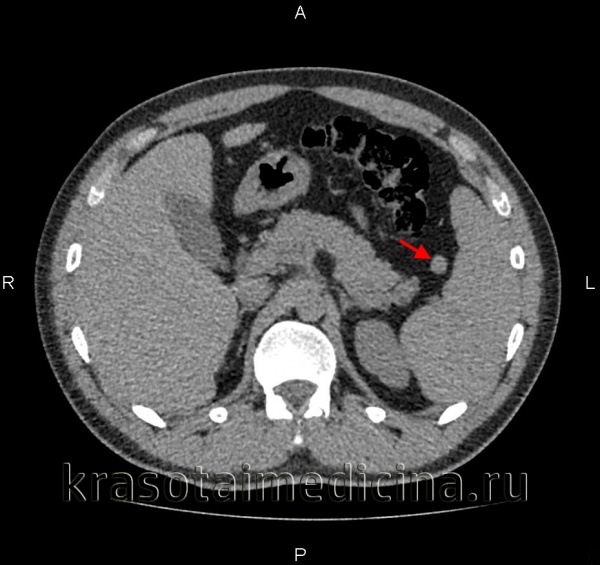

(Слева) На аксиальной КТ с контрастным усилением у пациента с неходжкинской лимфомой определяется выраженное увеличение селезенки с наличием опухолевых очагов с неоднородной структурой, слабо накапливающих контраст. Обратите внимание на лимфоидную инфильтрацию надпочечника и диффузное поражение внутрибрюшных лимфоузлов.

(Слева) На аксиальной КТ с контрастным усилением у пациентки, страдающей раком молочной железы, определяется метастаз в селезенке. Выявлены также несколько метастазов в печени (не продемонстрированы). Согласно результатам большинства исследований, рак молочной железы чаще всего обусловливает вторичное поражение селезенки.

(Справа) На аксиальной КТ с контрастным усилением определяется гиперваскулярное объемное образование в селезенке, которое было верифицировано как метастаз карциноидной опухоли желудка. Также опухоли селезенки необходимо дифференцировать с новообразованиями хвоста поджелудочной железы или других органов, располагающихся в поддиафрагмальной области слева.